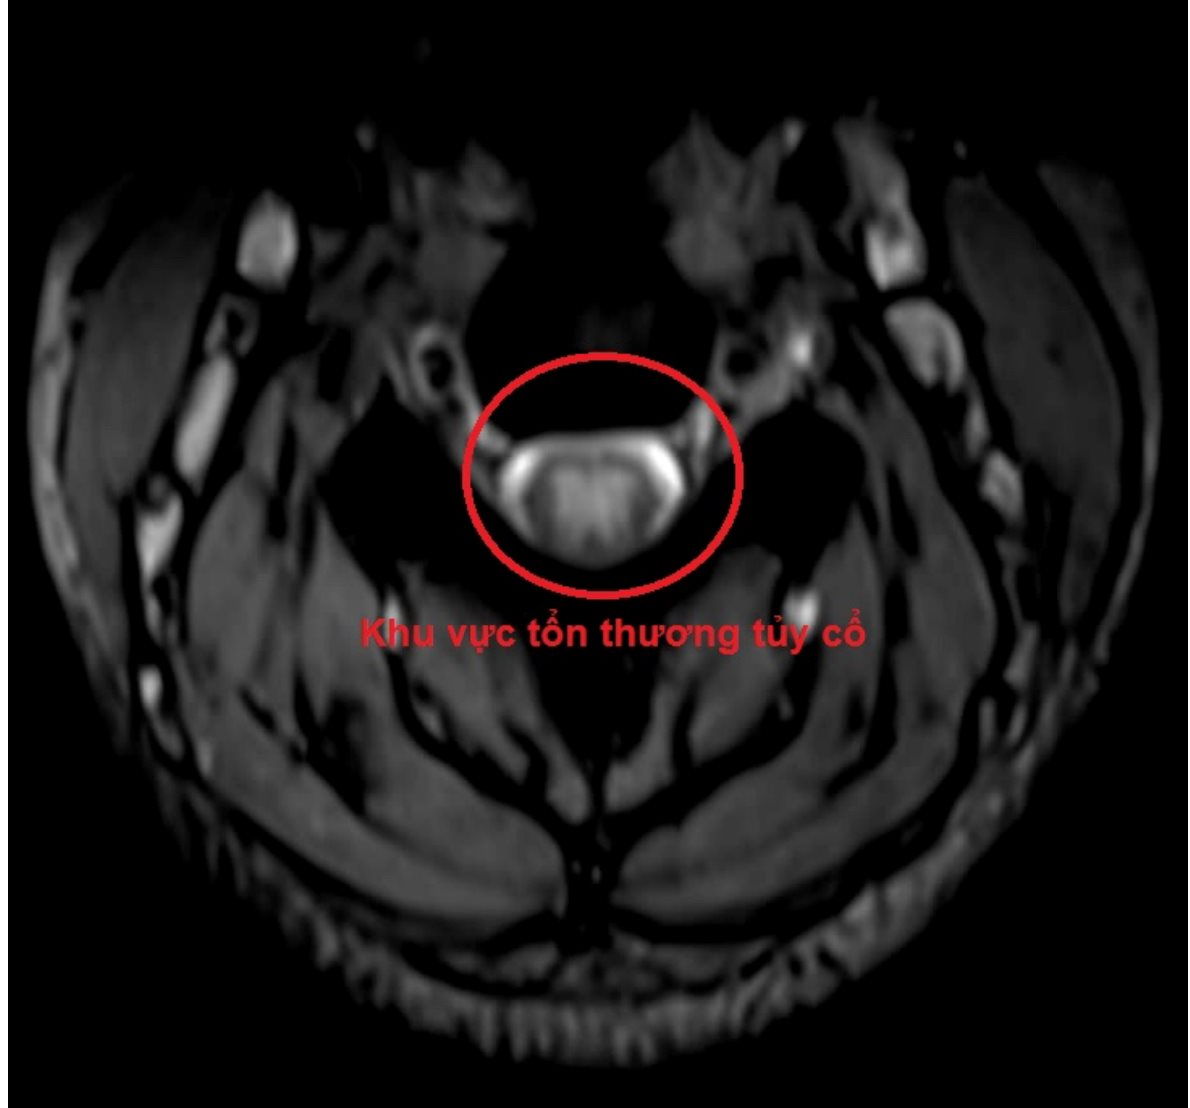

Chính vì vậy, trên những người bệnh có triệu chứng tê bì, dị cảm tứ chi, việc khai thác tiền sử lạm dụng bóng cười, khám lâm sàng và cận lâm sàng đầy đủ, đặc biệt là MRI cột sống cổ và đo dẫn truyền thần kinh sẽ giúp cho việc chẩn đoán chính xác. Từ đó sẽ phục hồi chức năng vận động của người bệnh một cách tối đa.